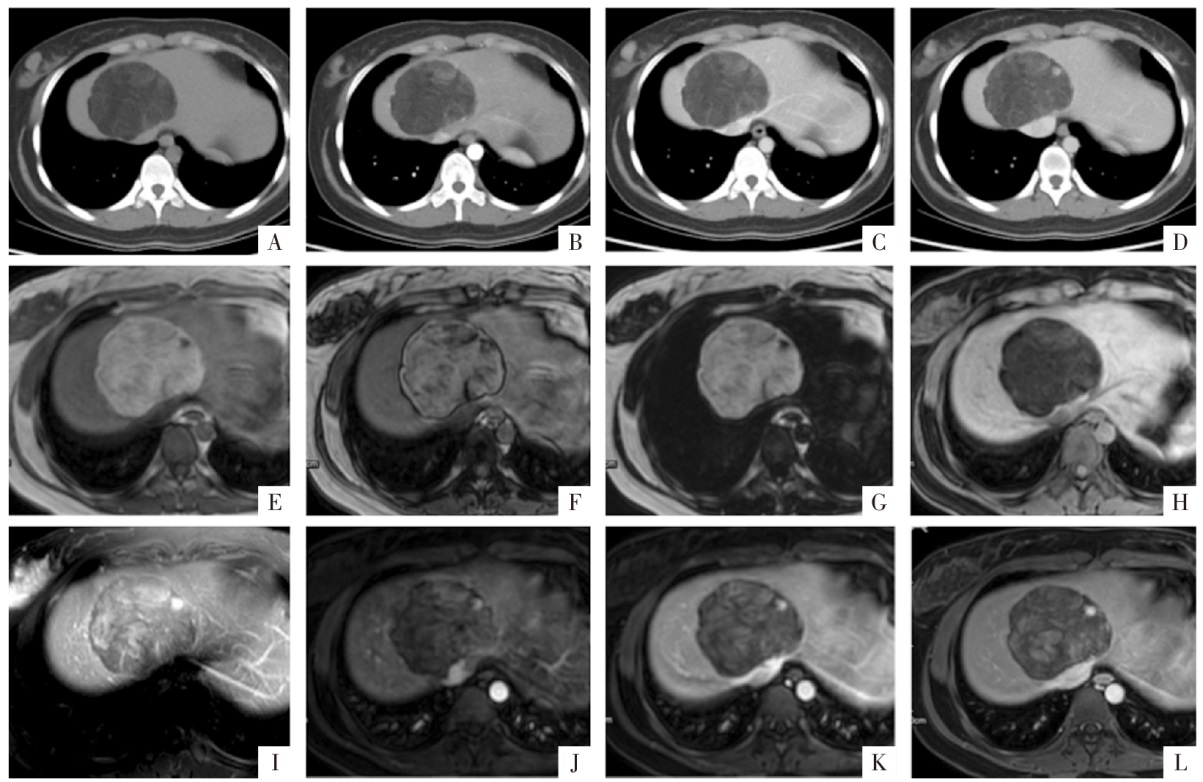

图12

病人女,25岁,HAML。A—D图分别为CT平扫、动脉期、门静脉期及延迟期影像,平扫CT值约-70 HU,增强扫描病变内软组织成分渐进性强化,部分点状结构延迟期强化较明显;E—H图分别为同相位、反相位、脂像及水像,病变基本以脂肪组织为主,反相位可见勾边效应;I图,T

2

WI上显示病变内信号混杂;J、K、L图分别为增强扫描动脉期、门静脉期、延迟期影像,强化特征同CT增强扫描,其中灶状明显强化的成分在T

WI上呈明显的高信号,为血管成分。